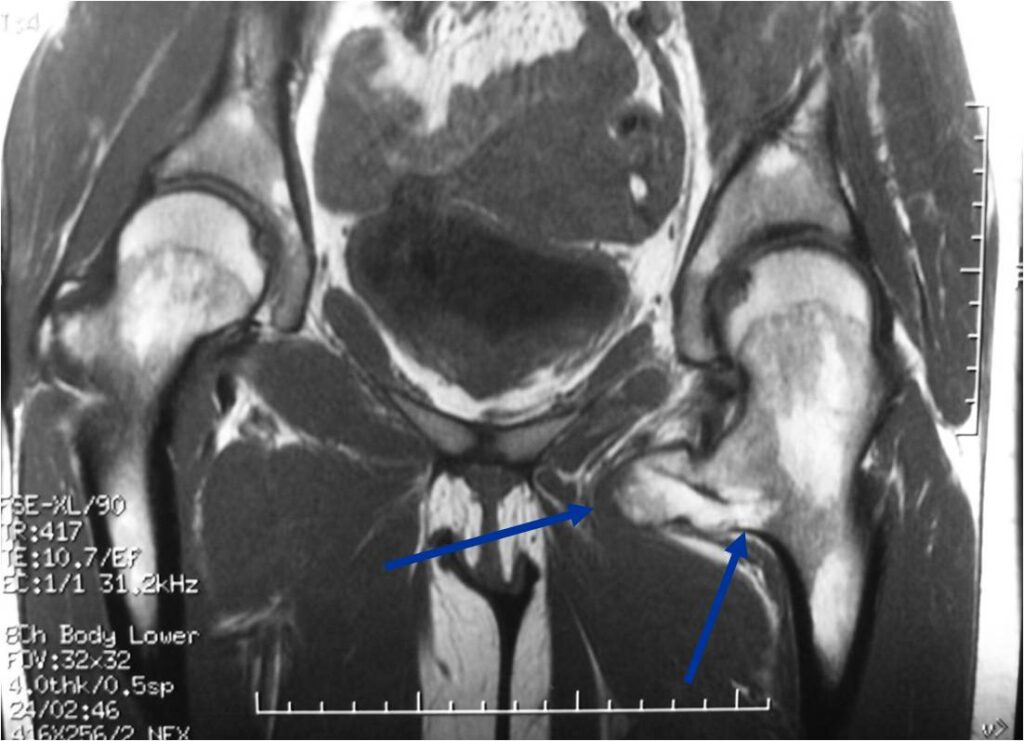

MRI: Secondary Chondrosarcoma of Proximal Femur: Thick Cartilage Cap (>2cm)

Malignant transformation is suggested by:

- Cartilaginous cap thickness greater than 2cm

- Cortical destruction

- Backgrowth of the cartilaginous cap into the stalk or medullary canal

- Lysis of calcifications in cap